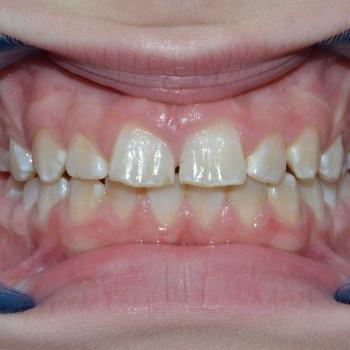

Gergő és édesanyja fogorvosi javaslatra keresett fel, a bal felső 2. kisőrlő hibás pozíciója miatt. A konzultáció során egyértelművé vált, hogy az előbb említett fog helyét teljes mértékben elfoglalták az előtte, illetve mögötte elhelyezkedő fogak, gyakorlatilag 0mm helyet hagyva a probléma megoldására. Ilyen esetekben felmerül a szájpadi irányba kiszorult fog eltávolítása, de a felső fogívben tapasztalható résesség a helyteremtés mellett szólt.

A kezelés első lépéseként Frog készülékkel hátrafelé mozdítottuk a bal felső első nagyőrlőt, ezzel elrendezve a nagyőrlők érintkezését, másfelől 4mm helyet teremtve a második kisőrlő számára. Ez a hely még nem volt elegendő, így rögzített fogszabályozóval zártuk a nagymetszők közötti, illetve az első kisőrlő előtti rést, mellyel további 2.5mm helyet nyertünk. Az így már 6.5mm-es rés elegendő volt ahhoz, hogy a kiszorult kisőrlőt bemozdítsuk a kívánt pozícióba, ezzel kialakítva egy funkcionálisan megfelelő és esztétikus felső fogívet. Mivel a harapás korrekciója, azaz a funkció helyreállítása kizárólag a felső fogív kezelésével is kivitelezhető volt, így a szülők nem kérték az alsó fogív torlódásának a megoldását.

A kezelés teljes időtartama: 2 év